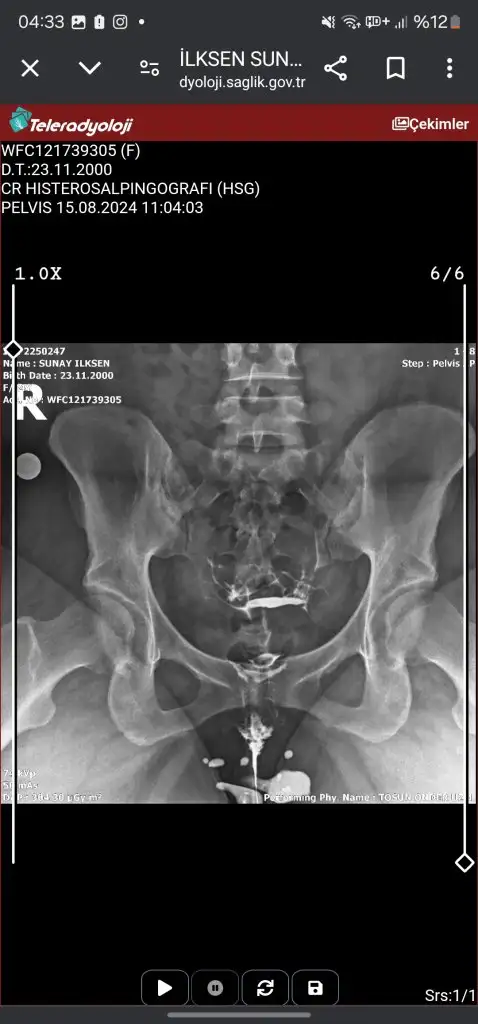

Canım tek tüpün kapalı galibaKızlar acil sonucuma bakarmısınızz ben hiçbirşey anlamıormm